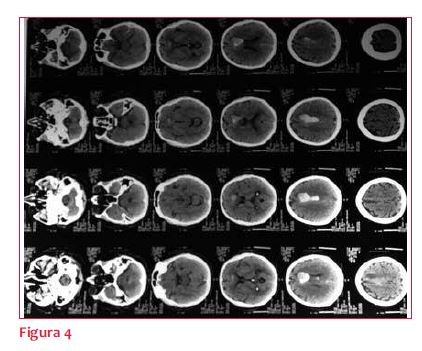

A las 24 horas instala parálisis facial central derecha y disartria. Tomografía de cráneo (TC) (figura 4): hematoma agudo frontal izquierdo. En acuerdo con neurólogo se decide continuar con controles clínicos y tomográficos en 24 horas y suspender la anticoagulación, no considerándose indicación de drenaje. La TC a las 48 horas evidencia persistencia de hematoma frontal izquierdo, sin cambios significativos. Se decide mantener sin anticoagulación por 15 días.